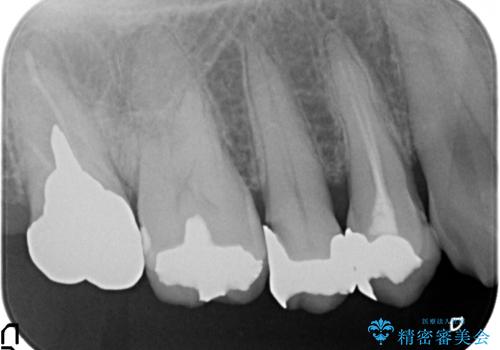

- 右上4番目の歯が黒くなっているのが気になるといらっしゃった方の症例です。

再根管治療後、オールセラミッククラウンによる補綴を行いました。

右上5も虫歯があったためオールセラミッククラウンによる補綴を行っております。

今回用いたオールセラミッククラウンはジルコニアフレームという白い素材の上にセラミックを盛っているため、審美性が非常に高いのが特徴です。

また、ジルコニアは人工ダイヤモンドの材料にも使われているほど高い強度を持っており、そのためオールセラミッククラウンは審美性だけでなく、奥歯やブリッジの補綴も可能とするクラウンです。